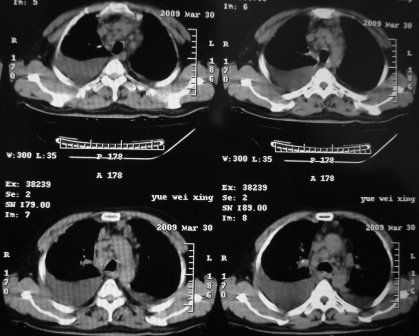

右肺下叶支气管中断闭塞,右下肺见不规块影,并胸腔积液,考虑肺中央型肺癌继发下叶不张,\\双侧胸腔积液,心包积液。

考虑右中央型肺癌并下叶不张,双侧胸腔积液,心包积液

右侧中央型肺癌伴右肺下叶不张,双肺及纵隔淋巴转移,双侧胸腔积液,心包积液。

1)考虑右侧中央型肺癌伴右肺下叶不张,双肺及纵隔淋巴转移。2)双侧胸腔积液,以右侧为甚。3)心包积液。

考虑右肺下叶中心性肺癌并纵隔淋巴结、双肺转移伴右肺下叶阻塞性肺不张;双侧胸水,右侧为著;心包积液